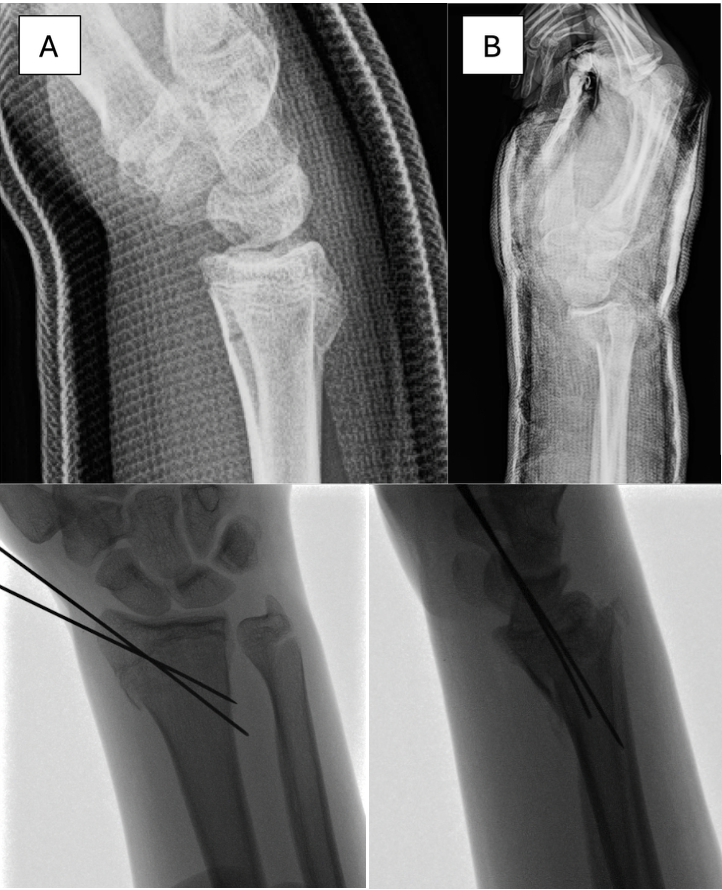

Patient two: A 15-year-old, right-hand dominant male presented to an outside emergency clinic with right wrist pain and obvious deformity immediately after falling off his electric bicycle. X-rays were obtained, and a reverse Colles fracture was diagnosed. While at the clinic, the patient developed an altered sensation over the median nerve distribution of his right hand, and he was sent to our hospital for a closed reduction procedure under general anesthesia. X-rays were obtained during the reduction to ensure proper alignment, and a Salter-Harris II right distal radius fracture and Salter-Harris I ulnar fracture were diagnosed. A plaster and fiberglass short arm cast was applied.

Five days later, at the patient’s first post-op follow-up, the patient reported well-controlled pain and was tapering off pain medications. Sensation was intact to light touch, and capillary refill was brisk on the right hand. X-rays showed a Salter-Harris II distal radius fracture with alignment intact. However, at follow-up two weeks after closed reduction, X-rays showed volar migration of the articular component of the radius and loss of reduction [Figure 3].